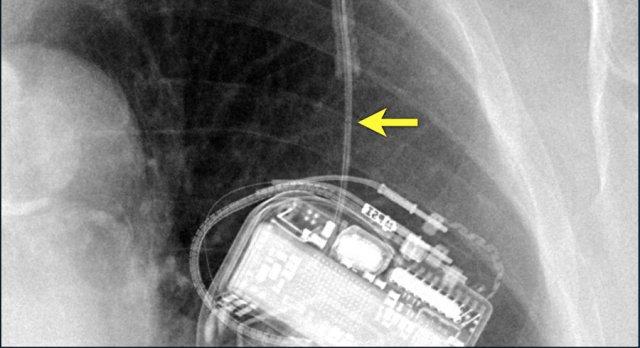

Hình ảnh gãy rõ ràng của một trong các điện cực.

Gãy điện cực kín đáo ở máy tạo nhịp tim hoạt động không bình thường.

Đường gãy cực kỳ kín đáo (mũi tên).